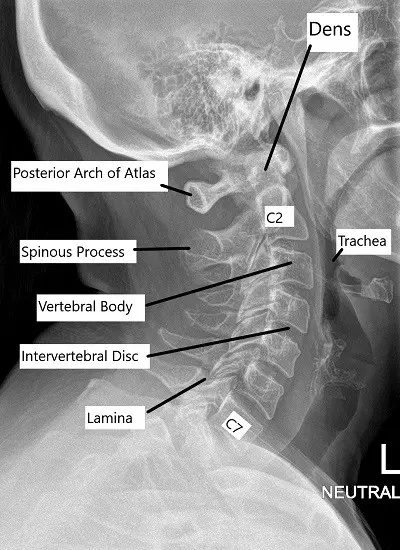

Visión general de la imagen

Las radiografías proporcionan una visualización básica de la alineación de la columna vertebral y la integridad ósea. Los TAC ofrecen imágenes detalladas de las estructuras óseas y son útiles en traumatismos o afecciones degenerativas. La RM es la mejor herramienta de diagnóstico por imagen para evaluar los tejidos blandos, incluidos los discos intervertebrales, los ligamentos, las raíces nerviosas y la médula espinal.

La resonancia magnética también puede mostrar hernias discales, compresión nerviosa y cambios postoperatorios, como la colocación de una prótesis discal cervical, un implante que restablece el movimiento en un segmento vertebral enfermo.

Columna cervical con disco protésico